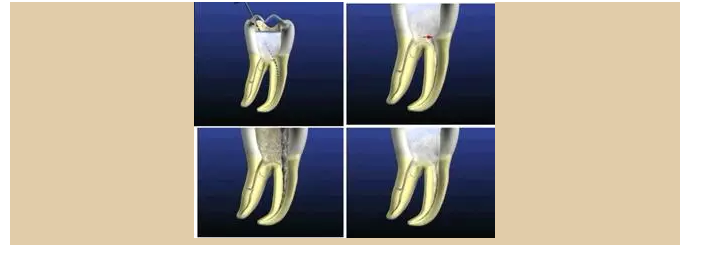

二、根管預(yù)備后形態(tài)

牙體缺損的修復(fù)需要將剩余牙體組織制備成一定形態(tài),以利修復(fù)體的良好固位。根管充填為了致密封閉根管系統(tǒng)也需要良好的根管預(yù)備后形態(tài)。

常規(guī)概念的根管預(yù)備后形態(tài)有: ( 1 )便宜形態(tài)( convenience form )。 ( 2 )保持形態(tài)( retention form )。

常規(guī)概念的根管預(yù)備后形態(tài)有:

( 1 )便宜形態(tài)( convenience form )。 ( 2 )保持形態(tài)( retention form )

( 3 )抵抗形態(tài)( resistance form )。

1. 便宜形態(tài)

便宜形態(tài)是自切端或咬頜面朝向根尖的直線開擴(kuò)尖錐形態(tài),減少污染物推出根尖孔,方便沖洗、根管充填和側(cè)壁施壓。

2. 保持形態(tài)

保持形態(tài)是根尖狹窄部內(nèi) 1 — 2mm 的一段距離,由擴(kuò)大器回轉(zhuǎn)切割而不貼根管壁提拉切割制成,是擴(kuò)大器的原始形態(tài)(近似平行)。在測試主牙膠尖時給測試者有一個牽引抵抗 (tugback) 的感覺。

3. 抵抗形態(tài)

抵抗形態(tài)是根管預(yù)備的根尖形態(tài),它是由擴(kuò)大器或根管銼尖端 75 度角自然切割而成。其目的是防止根管充填材超出根尖孔,并且使根尖封閉更加嚴(yán)密。